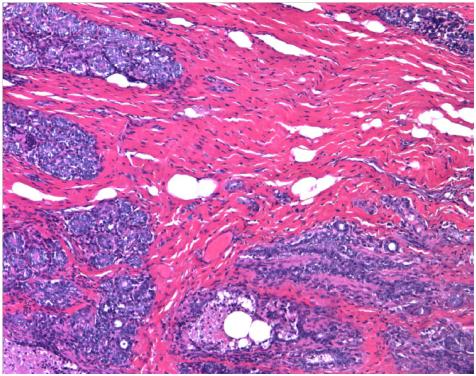

Breast cancer is the most common in women. One in nine will suffer breast cancer over their lifetime. Progress in prevention and early detection, and the use of chemotherapy after surgery (adjuvant chemotherapy), have achieved significantly increase survival in this disease in the last ten years, but much remains to be done.

The identification of patients with high-risk breast cancer is key to knowing whether a patient will require only the removal of the tumor by surgery or whether if she will need additional chemotherapy to make sure the removal of breast cancer cells. Currently, known genetic mutations and expression patterns are determined, but the puzzle of the genetics of the disease remains a large unfinished part.

"We've analyzed epigenetic alterations, namely the chemical signal called DNA methylation in 500 breast tumors and have compared the patterns obtained with the clinical behavior of these cancers," says Esteller.

"We note that there are two subgroups of breast tumors by epigenome: one which we have called Epi-Basal, characterized by loss of epigenetic marks causing breakage of chromosomes and the other that we have called Epi-Luminal B, that presents epigenetic inactivation of genes that should protect us from cancer and these altered cells can no longer do it".

The researcher highlights that "the subtype Epi-Luminal B behaves particularly aggressive form, and is associated with reduced survival of patients. This can be useful to recommend that these tumors do not be conformed to surgery and determine that it will probably be necessary to administer adjuvant chemotherapy in other words, in those tumors with a more 'benign' epigenetic pattern; surgery alone may be curative, thus avoiding the side effects of chemotherapy, "concludes the researcher.